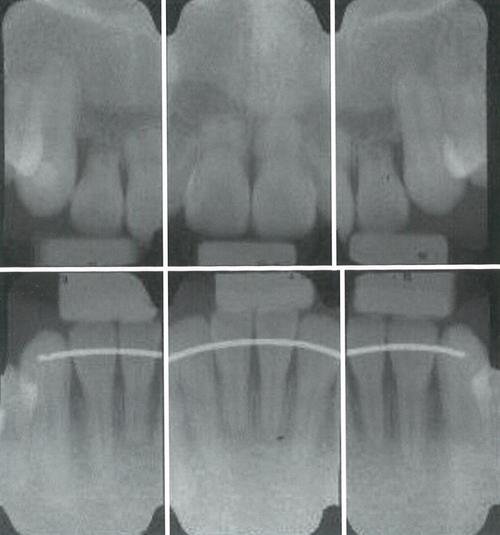

根据吸收部位和形态,牙根吸收可分为表面吸收、颈部吸收和内部吸收三种类型,表面吸收是最常见的类型,表现为牙根表面浅层、点状或线状的吸收,通常局限于牙骨质层,预后较好,多数可在去除矫治力后自行修复;颈部吸收则发生在牙根靠近牙颈部的区域,呈“碟形”或“沟状”缺损,由于该部位牙骨质较薄,吸收可能累及牙本质,严重时导致牙齿颈部薄弱,增加牙齿折裂风险;内部吸收较为少见,表现为牙髓腔或根管内壁的吸收,多与牙髓感染或创伤有关,若不及时处理可能发展为根尖周病变,临床诊断主要依靠X线检查,根尖片可显示牙根长度变化和吸收范围,而锥形束CT(CBCT)则能更清晰地呈现吸收的三维形态和程度,是目前诊断和评估牙根吸收的重要工具。

正畸中牙根吸收的临床表现因吸收程度而异,轻度吸收多无明显症状,常在治疗结束后复查时通过X线发现;中度吸收可能出现牙齿轻微松动、咬合敏感,但通常不影响功能;重度吸收则会导致牙齿明显松动、咬合疼痛,甚至牙根暴露,严重时需终止正畸治疗并保存患牙,目前临床常采用Andersen分级法评估吸收程度:1级(吸收<根长1/3)、2级(吸收1/3-2/3)、3级(吸收>2/3),其中1-2级多可继续治疗,3级需谨慎评估预后。

预防牙根吸收的关键在于规范治疗流程和个体化方案设计,治疗前需进行全面评估,包括拍摄根尖片和CBCT,了解牙根形态、长度及潜在风险因素,对高风险患者(如牙根弯曲、有吸收史)制定个性化矫治计划;治疗中应遵循“轻力矫治”原则,优先使用镍钛丝等轻力材料,避免过大矫治力,控制牙齿移动速度,尤其是扭转、压低等高风险移动;同时定期复查(每6-12个月拍摄根尖片),动态监测牙根变化,一旦发现吸收迹象及时调整矫治方案,如减小力值、延长复诊间隔或暂停加力。